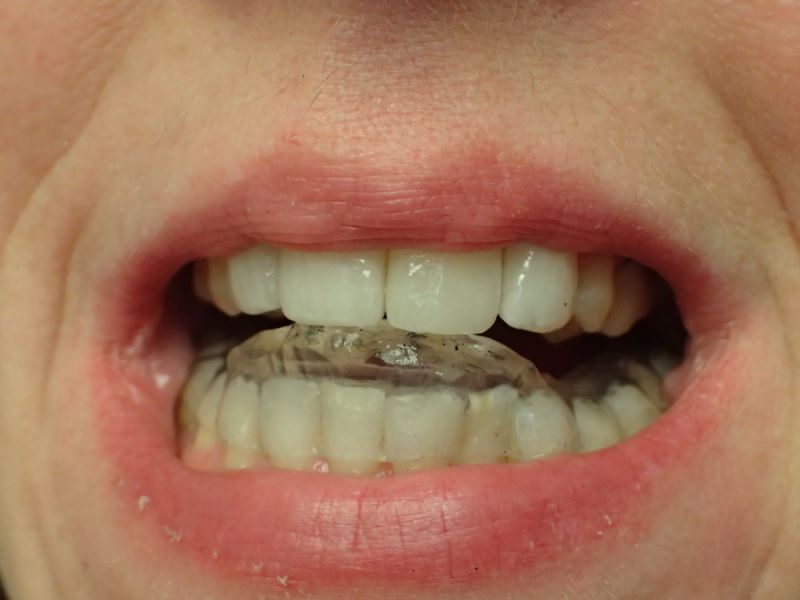

Patientin von der dänischen Grenze erhält einen adjustierten Aufbissbehelf